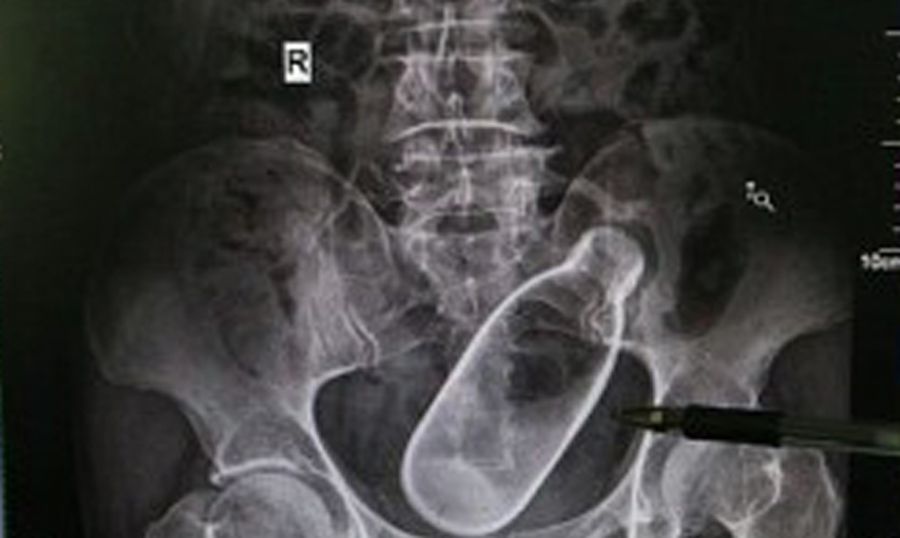

Una semplice radiografia, talvolta, può risultare risolutiva per scoprire in maniera semplice e veloce quanti e quali oggetti si possono trovare infilati all’interno del corpo umano. Coloro che lavorano nei pronto soccorso degli ospedali sanno bene che ogni giorno può accadere di tutto, i motivi per cui si richiede una prestazione sanitaria possono essere i più disparati, e il sangue freddo è fondamentale in certi casi, può fare la differenza tra la vita e la morte. Spesso però, tra le emergenze mediche si elencano situazioni davvero imbarazzanti ed insolite, che sicuramente scatenano la curiosità, ma che talvolta non bisognerebbe approfondire troppo, per non rischiare di venire a sapere la verità!

Un altro avvocato trentanovenne ha invece richiesto l’aiuto dei medici per farsi estrarre un flacone di profumo dal sedere, e un altro professionista che ha voluto restare anonimo per motivi di privacy, è invece stato operato per togliere dal condotto anale, un barattolo di burro di arachidi. Il nome non lo sappiamo, ma la sua radiografia ha fatto il giro del web.